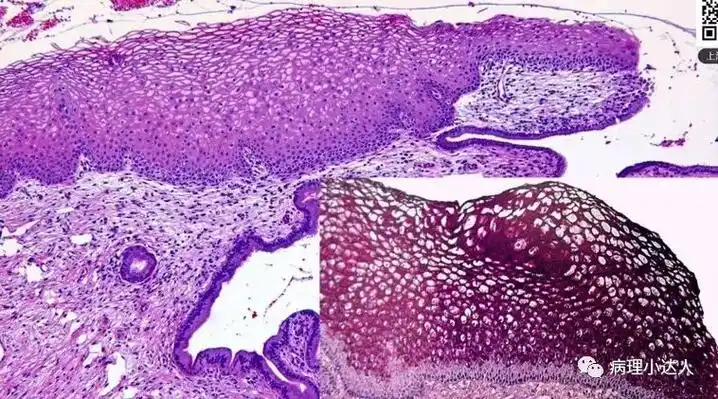

【学习笔记】低级别鳞状上皮内病变的诊断与鉴别诊断